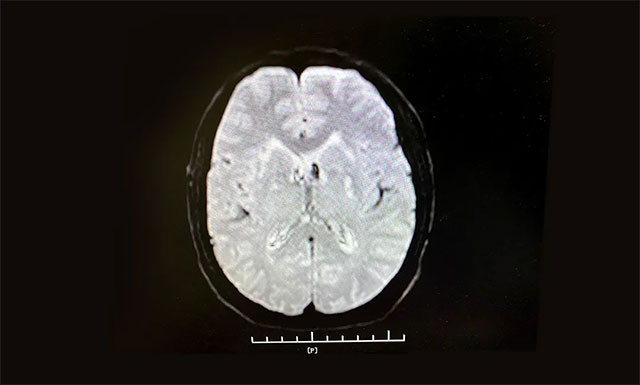

从急诊科11:11接诊,11:13建立静脉通道,到11:28影像科CT平扫排除脑出血,并告知家属,经反复沟通到11:56接受溶栓,门诊、急诊科、脑血管病科、影像科、检验科等多个科室通力合作,发挥多学科联动优势,无缝对接,DNT (Door to Needle Time——从患者入院急症科到接受溶栓治疗时间)用时为45分钟,为抢救患者的大脑功能赢得了宝贵时间。

▲ 根据急诊CT影像结果,排除患者脑出血

张琪主任指出,由于脑组织对缺血和缺氧非常敏感,一旦发生脑梗,如果未得到及时救治,患者将以每分钟190万个神经元细胞死亡的速度丧失脑神经功能,尤其是发病时间超过4.5小时后,脑细胞就会出现不可逆转地死亡。因此,对于脑梗患者应在发病4.5小时内尽可能静脉溶栓治疗,在发病6-8小时内,到有条件的医院可进行适当的急性期血管内干预。